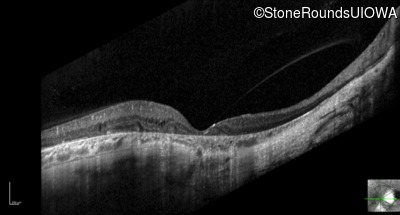

Optical Coherence Tomography - Right - 20/50 sc

Exemplar / OCT Stack